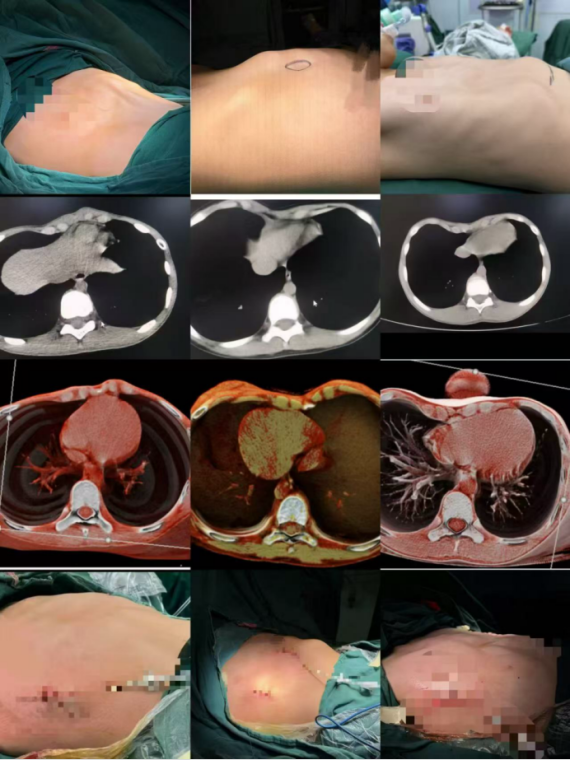

1. 漏斗胸:这是最常见的类型,发病率约为1/300,男孩多见。表现为胸骨中下部及其相连的肋软骨向内凹陷,形成一个“坑”状或“漏斗”状的畸形。

2. 鸡胸:发病率次于漏斗胸。表现为胸骨及其相连的肋软骨向前凸出,像“鸡的胸脯”一样隆起。凸起可以是整个胸骨,也可能偏向一侧。

矫形手术主要有NUSS手术、WANG手术、WENLIN手术,均具有安全性高、矫形确切、微创损伤小、恢复时间短等优点。各个术式治疗不同的畸形,手术方式由有经验的医生根据病情、年龄等决定。